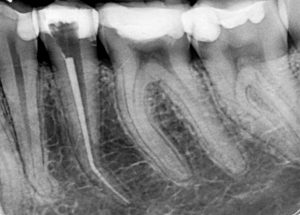

Случай на релечение на долен пети зъб, в който предишният колега беше фрактурирал канален инструмент и в опита си да довърши

лечението бе перфорирал и корена на нивото на извивката.

Освен перфорацията, извивката и счупения канален инструмент,

сложността на случая идваше и от факта, че коренът беше изключително тесен в областта на

извивката и имаше голяма опасност при

премахването на инструмента зъбът допълнително да се отслаби на

това място.

След изключително щадящо премахване на инструмента,

каналът бе обработен до невероятните 27 мм.

След което, заедно с перфорацията, беше запълнен с

биокерамичен сийлър